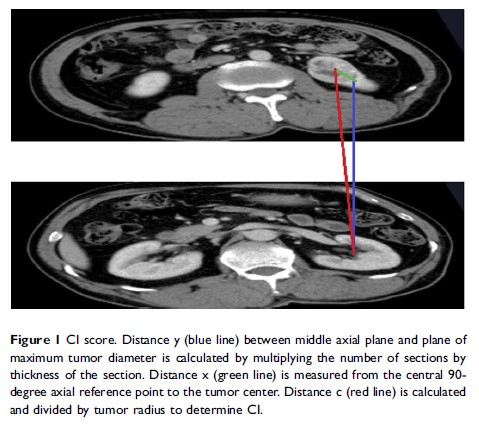

使用向心性指数的新术前诺模图用于预测核分级较高的透明细胞肾癌